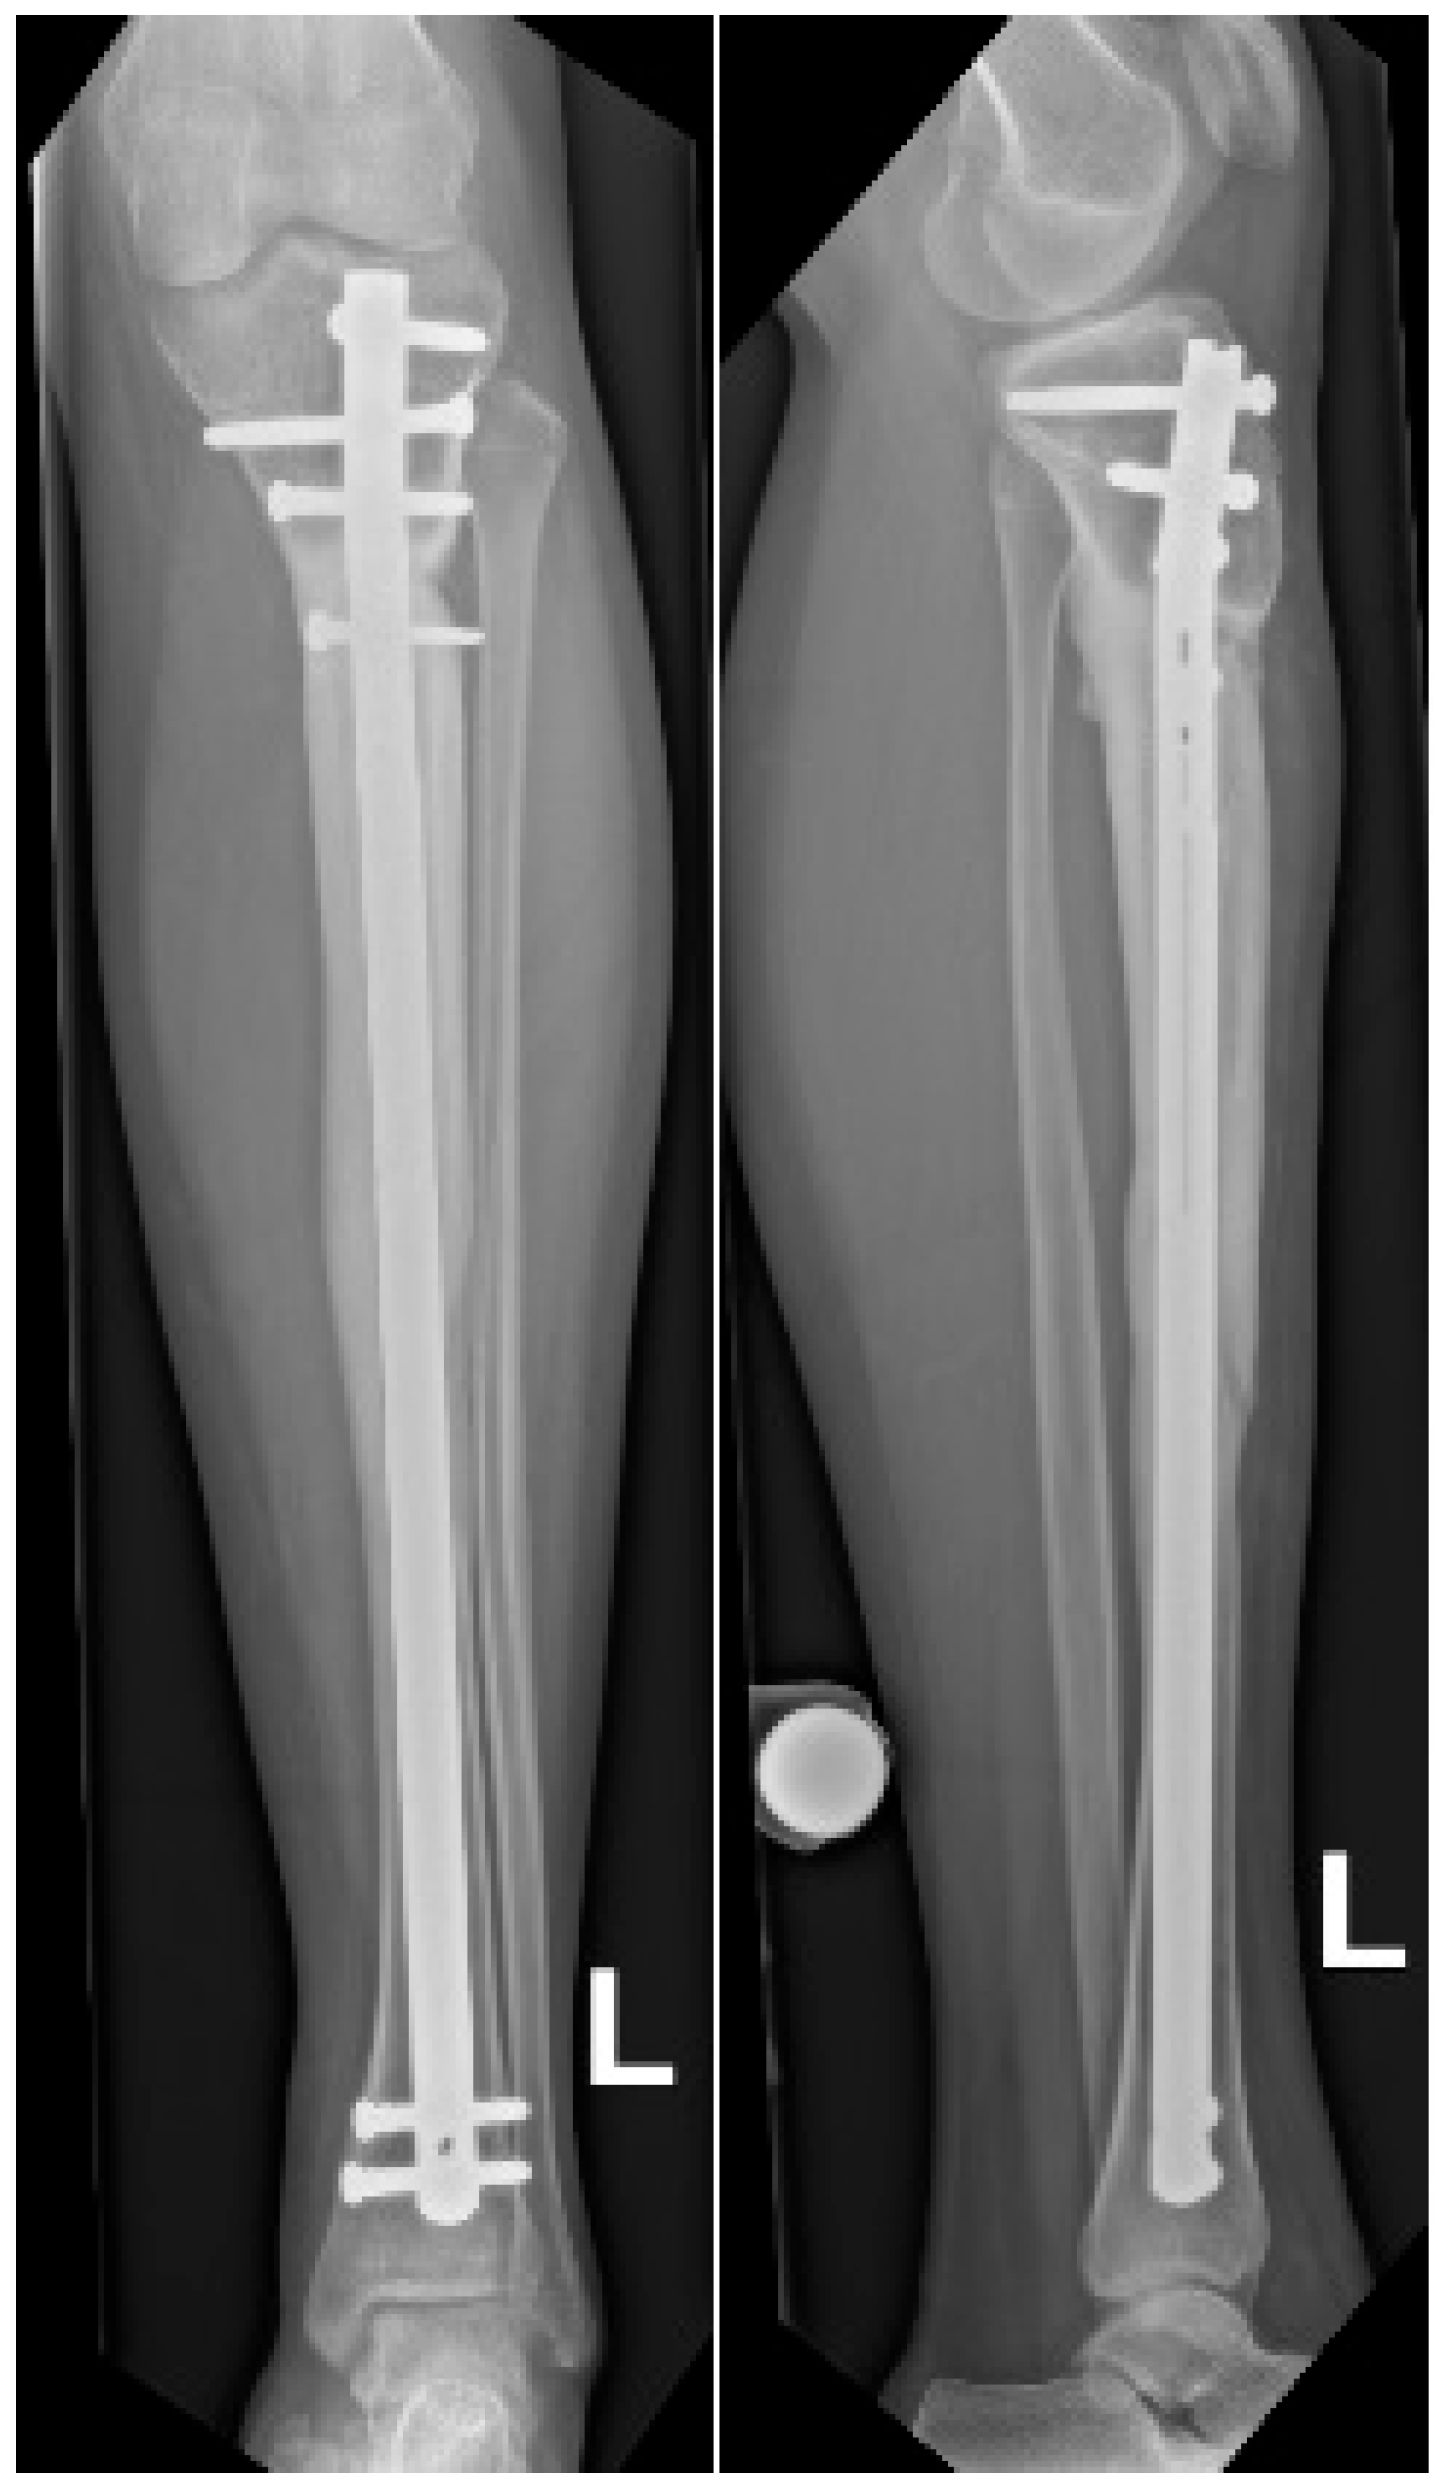

At 18 months postoperatively, radiographs confirmed complete consolidation at both the docking and distraction sites (Figure 7). At two years postoperatively, complete hardware removal was performed (Figure 8).

Figure 7.

Radiographs at 18 months follow-up showing anteroposterior view (left) and lateral view (right) of the tibia. Consolidation can be observed, demonstrated by bridging callus across cortices and the absence of visible fracture lines, with restoration of tibial alignment.